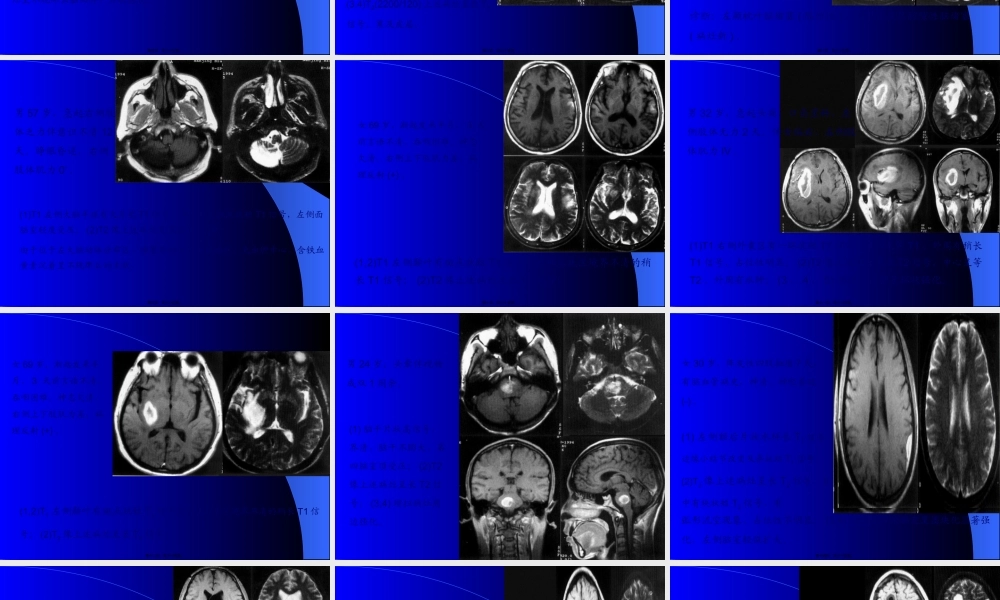

延髓颈髓蛛网膜下腔左侧椎动脉硬膜外脂肪第一页,共三十五页。女39岁,双上肢麻木,肉跳手变细2年。双上肢肌萎缩,肌力III-IV,颈5以下痛觉减低。T1小脑扁桃体及延髓下疝至颈椎管内颈3-胸4脊髓中央管扩张;FLASH(500/45/35)枕大池颅内外段消失,延髓中央管闭塞,颈1-2后纵韧带增厚钙化第二页,共三十五页。男55岁,左顶受击后头痛半月,以左侧面为主,无呕吐。体征:左侧面部角觉敏感。T1(360/11)左侧顶叶颅板下类梭形短T1病灶,皮质受压,脑室系统无改变,T2(2200/120)上述病灶呈长、短混杂改变。第三页,共三十五页。男59岁,急起双下肢无力三天,1月前有轻微头部外伤史。伸舌偏右,双下肢肌力IV,左侧上肢张力增高,左侧巴氏征(+)。T1(360/11)两侧额叶脑外大片长梭形短T1病灶,局部皮质受压,大脑纵短T1病灶;T2(2200/120)上述病灶呈长T2及混杂T2改变;T1(320/15)上述病灶呈短T1,两侧脑室、前角受压,变形,下移。第四页,共三十五页。女58岁,反复头痛伴双眼视力下降1年,左肢体无力三天。左侧中枢性面瘫,左上肢肌力III-IV。(1,2)T1(360/11)右侧额叶顶见大片低信号,脑组织介面不清;(3,4)T2(3300/120)上述病灶呈长T2信号;(5,6)增强T1(320/15)上述病灶呈不规那么脑回样、片状强化。第五页,共三十五页。男43岁,急起右侧肢体无力,言语不清1小时。神志清,右侧肢体肌力IV。(1,2)T1(360/11)左侧额顶颞叶顶见大片稍长T1信号,其间有小块状T1改变,占位效应显著,右侧脑室体旁小点状长T1信号;(3,4)T2(2200/120)上述病灶呈长T2信号,累及皮层。第六页,共三十五页。男58岁,急性头痛,言语不清2天。1年来反复发作;失语,伸舌偏右,右半身肌力差。(1,2)T1左颞枕叶大片长T1信号,左侧基底节点状长T1信号;信号;(3,4,5)T2像上述病灶呈长T2信号;诊断:左颞枕叶脑堵塞(陈旧性);左侧基底区腔隙性脑堵塞(病灶新)。第八页,共三十五页。男57岁,急起右侧肢体乏力伴意识不清12天。睁眼昏迷,右侧肢体肌力0。(1)T1左侧大脑半球有大片长T1信号,其中可见斑点状短T1信号,左侧面脑室轻度受压;(2)T2像上述病灶呈混杂T2信号;由于位于左大脑动脉分布区,堵塞后出血多为瘀斑状,无血肿中心,含铁血黄素沉着呈不规那么的点状。第九页,共三十五页。女69岁,渐起发呆半月,3天前言语不清、吞咽困难。神志欠清,右侧上下肢肌力差,病理反射(+)。(1,2)T1左侧颞叶有斑点状短T1信号及右侧基底区境界不清的稍长T1信号;(2)T2像上述病灶呈长T2信号;第十页...